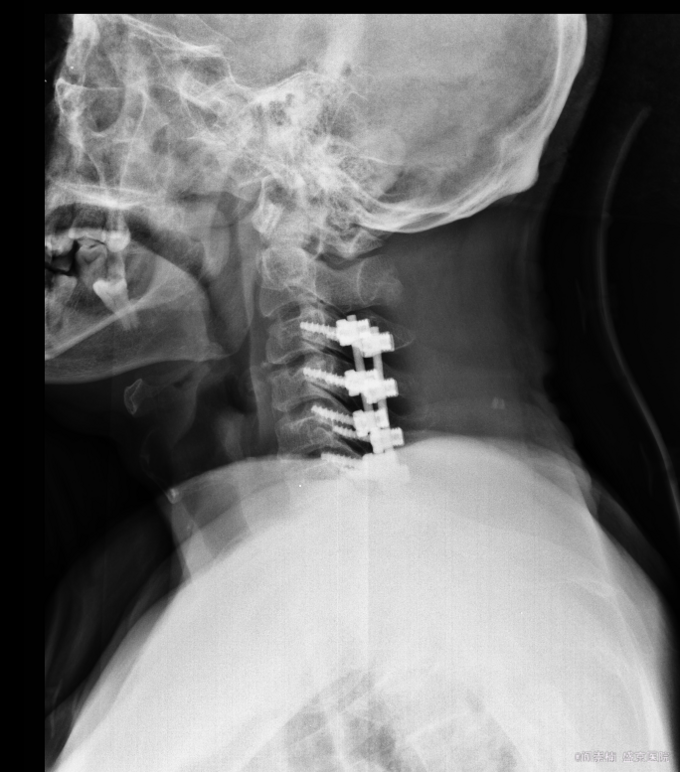

患者入院后完善相关检查,明确诊断,手术指征明确,于2015-11-17日于全麻下行颈椎后路单开门椎板减压,侧块螺钉内固定术,术后经抗炎、止疼等对症治疗后,患者恢复顺利,切口愈合良好,今日可出院。